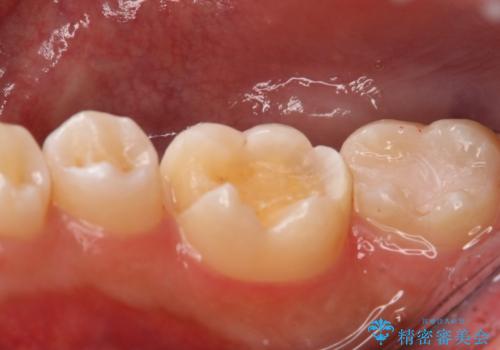

上はう蝕が歯頚部まで達していたのでクラウンでの治療を選択しました。

銀歯直下もう蝕が進行していたので全て除去した上でCRにて裏層しています。